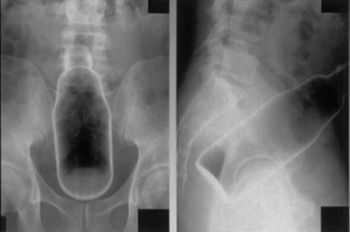

中国のある男性は自身の肛門に“液体のり”を容器ごと挿入。

抜けなくなり、病院に駆けつけるハメになったという。

男性の話からそれが円柱形の容器に入れられた液体のりであることも判明した。

しかし、のりはすでに男性の体内奥深くにまで侵入し、容器も滑りやすい素材で容易には引き抜けない状況。

のりの容器は長さ15センチ、直径5センチほどの大きさだった。